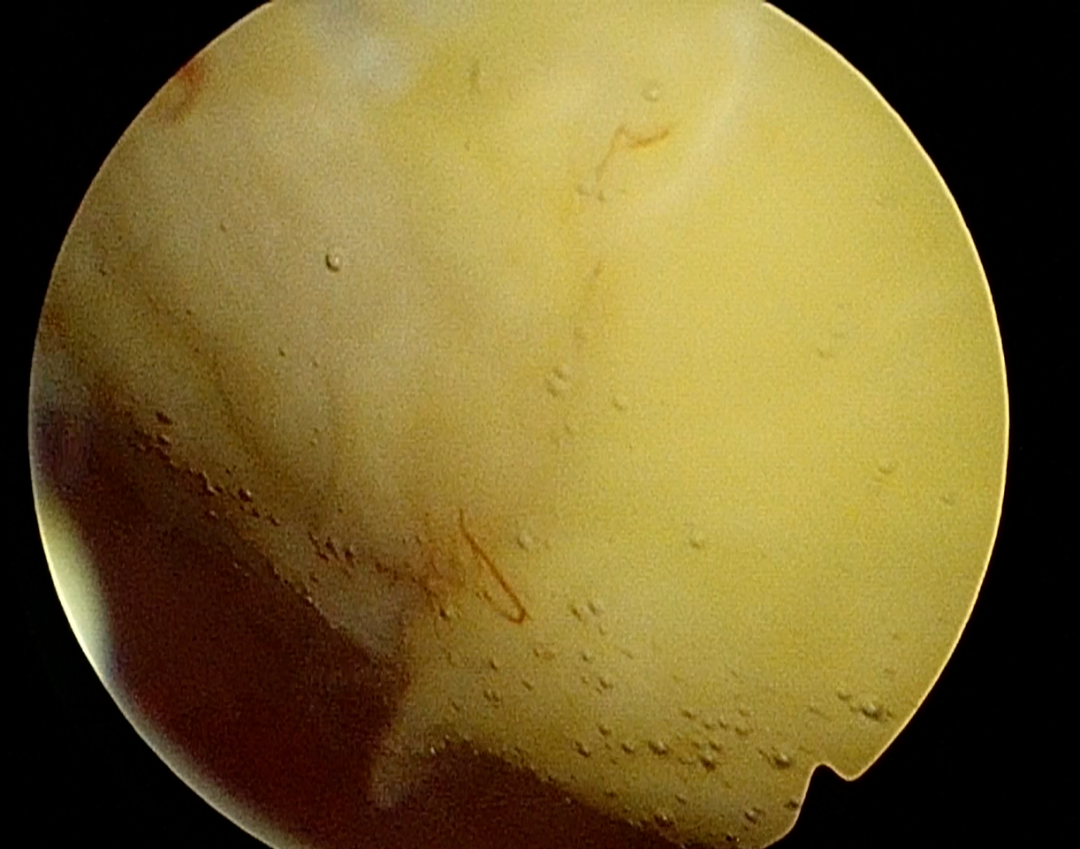

夏教授为患者安排了三维超声和宫腔镜检查,结果显示肌瘤位于宫底后壁,2-5型贯穿整个肌层,直径95mm,周边血流丰富。如果选择腹腔镜手术剔除肌瘤,子宫肌层完整性受到破坏,存在瘢痕子宫妊娠子宫破裂风险,宫腔镜手术创伤更小恢复更快,患者有生育计划,如果能通过宫腔镜手术治疗,是对生育功能最大的保护。但巨大的肌瘤马上手术,风险太大。夏教授决定先予GnRH-a类药物治疗手术预处理,缩小肌瘤体积,改善贫血后择期手术。4个月治疗后,血色素正常,宫腔镜检查显示肌瘤继续向宫腔突入,但仅稍微缩小至直径88mm,这对于宫腔镜手术仍然是个挑战。从“手术安全是第一位”的角度出发,夏恩兰主任和彭雪冰主任决定腹腔镜监护下进行宫腔镜手术,根据术中情况随时调整手术方式,“进可攻,退可守”。 术中见肌瘤突向并充满了宫腔,手术初始,宫腔可操作的空间十分有限,彭主任用娴熟的宫腔镜手术技术迅速高效切除缩小肌瘤。这一过程需要面临出血、灌流介质过度吸收综合征、子宫穿孔等重重风险。麻醉医师龚璠在手术过程中,密切关注患者生命体征为手术保驾护航。终于,在不懈的努力下,完全切除了这一巨大肌瘤,去除了导致患者大出血的元凶,也守卫了“生命宫殿”,为患者保留了生育的希望。术后患者恢复良好,顺利出院。 宫腔镜诊治中心成立32年,诊治患者数以万记计。在夏恩兰教授的引领下,宫腔镜诊治技术日益精湛,不仅保留子宫,而且保护子宫的功能,提高生育力。最初宫腔镜下子宫肌瘤切除术用于处理0、1、2型肌瘤,而现在3型、甚至2-5型的巨大肌瘤也可以通过宫腔镜手术来切除,术后2-3个月创面完全愈合,保护了生育功能,是患者的福音。 宫腔镜诊治中心在夏恩兰教授及黄晓武教授的带领下,全科医务人员齐心协力,勇于实践,精益求精,不断总结经验、提高技术,为广大患者提供更优质的医疗服务。